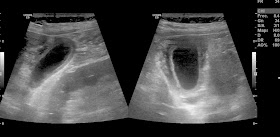

sesión de casos de abdomen miercoles 20 de noviembre de 2013 (AHB)

Paciente que consulta  por empeoramiento de su estado basal, disnea, tos y expectoración

le objetivan al ingreso insuficiencia renal crónica reagudizada, hematuria, neumonía basal derecha y una pielonefritis.

Le piden la ecografía basicamente por la hematuria, el aumento de la creatinina y dolor abdominal difuso a la palpación.